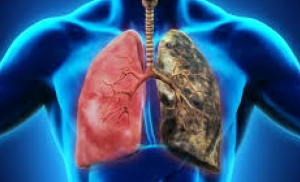

ХОБЛ

Интерстициальные заболевания легких